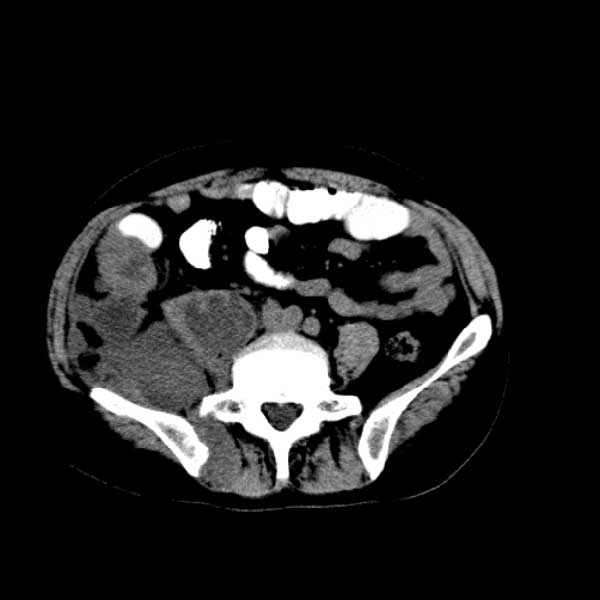

标题: CT13513:男 71 腹部疼痛20余天,近几天高热就诊,骨窗未见异 [打印本页]

标题: CT13513:男 71 腹部疼痛20余天,近几天高热就诊,骨窗未见异

考虑感染性病变可能性大,起源于阑尾?

感染,脓肿形成

考虑为化脓性阑尾炎.脓肿形成.及多肌肉累及.

考虑右侧腰大肌脓肿,向右髂窝、右腹股沟流注。

支持化脓性阑尾炎伴右髂窝脓肿、腰大肌腰方肌脓肿形成。

考虑腹腔及盆腔化脓性炎症,累及右侧髋关节及腹股沟区.

首先考虑化脓性阑尾炎伴腰大肌、腰方肌脓肿,不除外回盲部结核。

回盲部癌待排除。

患者肠镜检查考虑结肠癌,病理证实

患者肠镜检查考虑结肠癌,病理证实。肺部ct可见多发结节,考虑转移